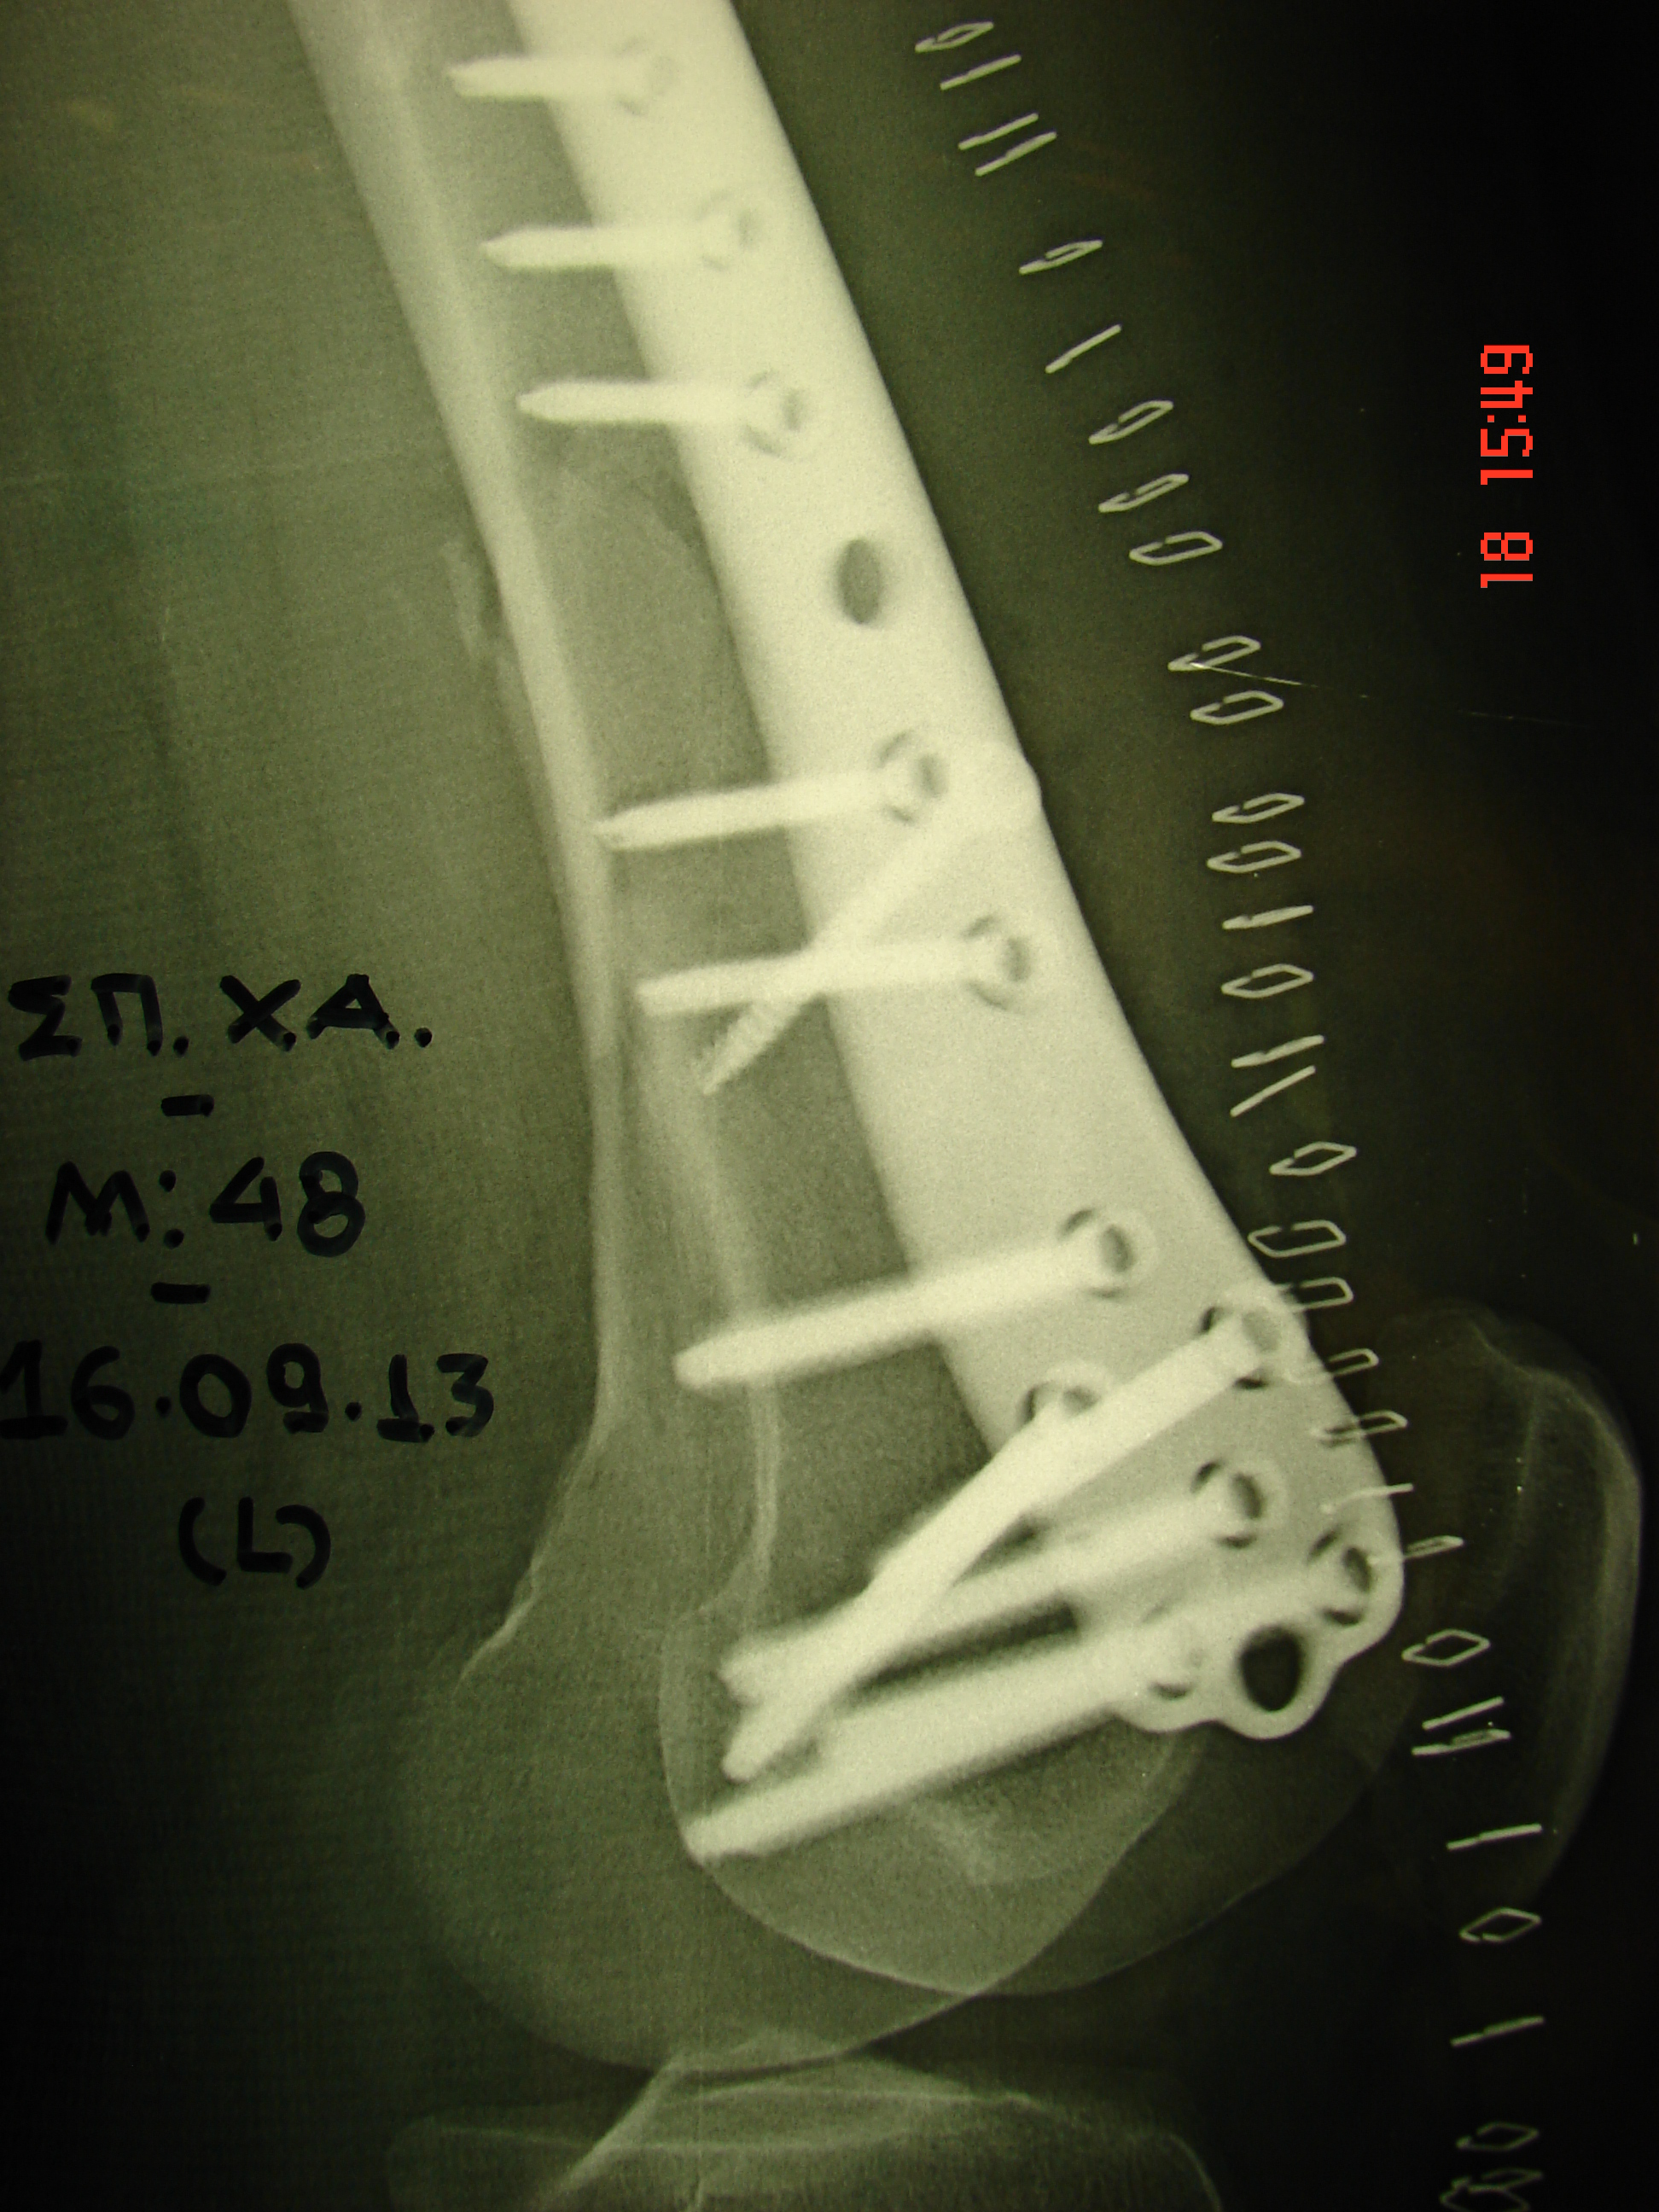

Για την ανάταξη και σταθεροποίηση του κατάγματος, υποβλήθηκε σε χειρουργική επέμβαση με χρήση ειδικής πλάκας οστεοσυνθέσεως.

Εικόνα 2 α,β,γ,δ

Μετεγχειρητικές προσθιοπίσθιες και πλάγιες ακτινογραφίες: Ανάταξη και οστεοσύνθεση του συντριπτικού κατάγματος

Η μετεγχειρητική πορεία υπήρξε πολύ καλή. Η κινητοποίηση του τραυματία εγένετο βάσει των καθορισμένων προδιαγραφών αρχίζοντας με τη μη φόρτιση του σκέλους αρχικά και προοδευτικά αυξανόμενη περαιτέρω φόρτιση, εώς ότου ανεξαρτητοποιήθηκε πλήρως. Το εύρος κίνησης της αριστερής άρθρωσης του γόνατος υπήρξε εξαιρετικό.

Στον 8ο μετεγχειρητικό μήνα παρατηρείται εξέλιξη της πορώσεως του κατάγματος και σταθερή οστεοσύνθεση